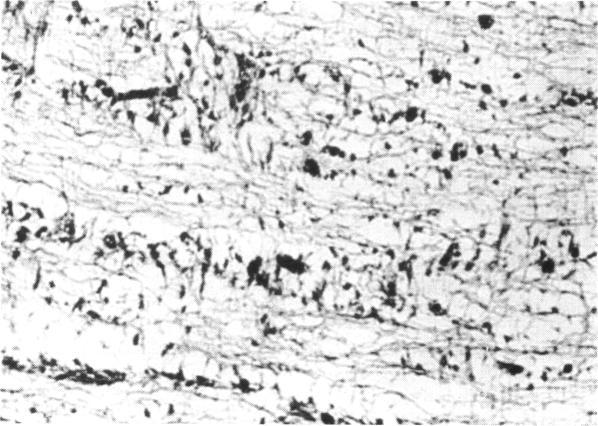

Ocular pathology of the Majewski syndrome.

Br J Ophthalmol. 1982 Nov;66(11):736-41. doi: 10.1136/bjo.66.11.736.